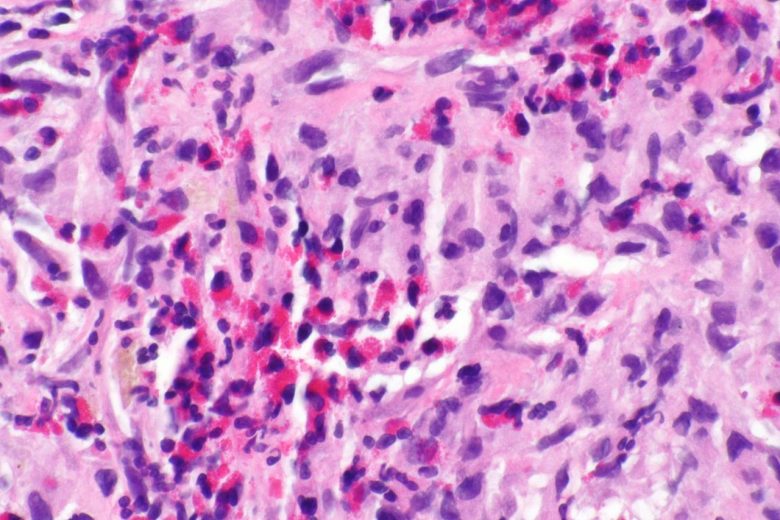

Image Credit: Lance Liotta Laboratory / Wikimedia Commons.

Adrenocortical cancer

“Adrenocortical carcinoma is a rare disease in which malignant (cancer) cells form in the outer layer of the adrenal gland… Having certain genetic conditions increases the risk of adrenocortical carcinoma.

“Symptoms of adrenocortical carcinoma include pain in the abdomen… Imaging studies and tests that examine the blood and urine are used to detect (find) and diagnose adrenocortical carcinoma. Certain factors affect the prognosis (chance of recovery) and treatment options.”